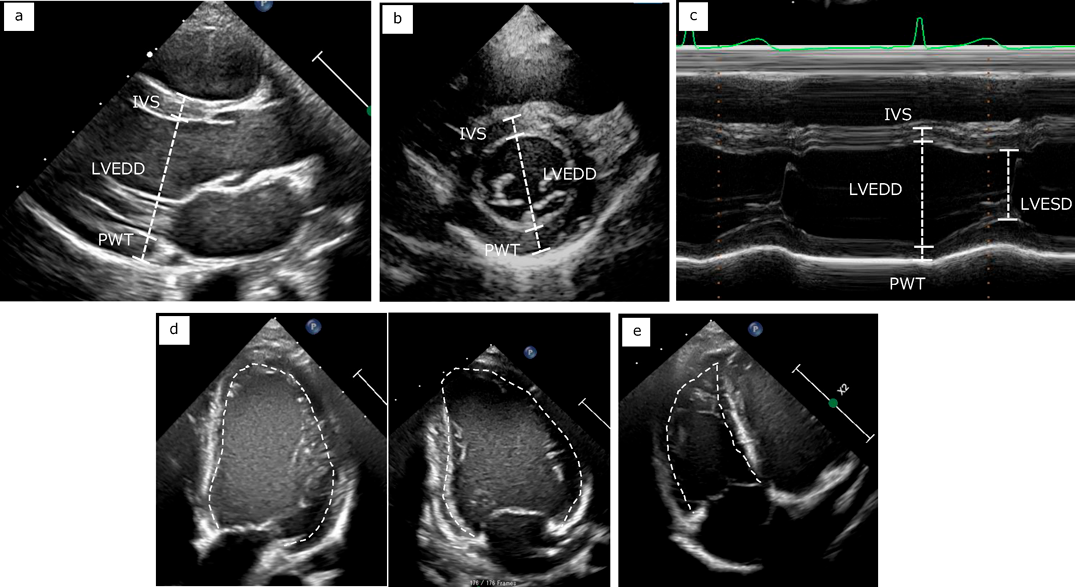

左室内径は傍胸骨左室短軸断面の断層像で計測することが小児のガイドラインでは推奨されているが,同断面でのMモード法も広く用いられている3).一方成人のガイドラインでは左室長軸断面での計測が推奨されている4).Mモード法は,必ずしも心臓の長軸に対して垂直にならないこと,心臓そのものの動きにより心周期を通して同じ部位を計測できないことなどから,最新のガイドラインでは断層像での計測が推奨されている.Mモード法ではleading edge to leading edge,断層法ではtrailing edge to leading edgeで計測する.これら左室内径の計測値から左室容積や駆出率を算出する方法が用いられてきたが,いずれも一つの内腔計測からでは正確性に限界がある.より左室形態の変化を反映させる方法として四腔断面と二腔断面からのdisc summation法が推奨される.注意点としては二断面での左室長軸長の差が10%以下になるように描出する必要があり,ダイナミックレンジを狭くするなど心内膜面を明瞭に描出してトレースしなければならない(Fig. 4).

Pediatric Cardiology and Cardiac Surgery 41(1): 20-27 (2025)

Fig. 4 Measurement of chambers

a. Left ventricle long axis measurement. b. Left ventricle short axis measurement. c. Left ventricle measurement using M-mode method. d. Left ventricle measurement using bi-plane disk summation method. e. Right ventricle measurement. IVS, interventricular septal wall thickness; LVEDD, left ventricle end-diastolic dimension; LVESD, left ventricle end-systolic dimension; PWT, posterior wall thickness.

右室計測にはその形態から複数の断面を描出する必要があるが,複雑な構造のために検者間誤差も大きくなる.右室焦点四腔断面で基部径,中部径,断面積を,傍胸骨断面で流出路径を計測する.断面積の拡張末期と収縮末期の差を拡張末期面積で除した値をfractional area change(FAC)として右室収縮能の指標とする.また三尖弁輪径の移動距離(TAPSE)も簡便に測定できる指標である.